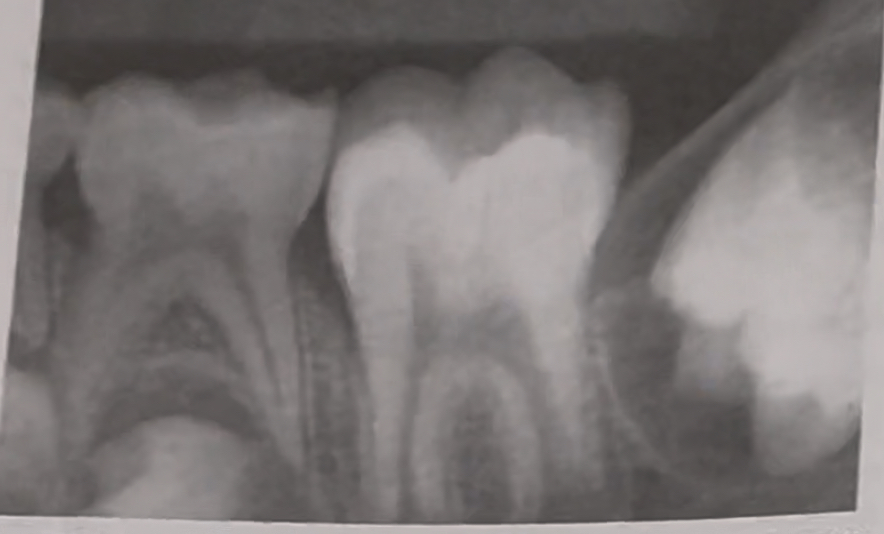

Impaction in mixed dentition |

unerupted supernumerary teeth

Impacted third molar |